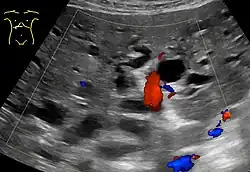

Intrahepatic bile ducts compose the outflow system of exocrine bile product from the liver.

They can be divided into:[2]

- Lobar ducts (right and left hepatic ducts) - stratified columnar epithelium.

- Interlobar ducts (between the main hepatic ducts and the interlobular ducts) - pseudostratified columnar epithelium.

- Interlobular bile ducts (between the interlobar ducts and the lobules) - simple columnar epithelium.

- Intralobular bile ducts (cholangioles or Canals of Hering) - simple cuboidal epithelium, then by hepatocytes

- Bile canaliculi - two half-canaliculi formed by the hepatocytes facing the perisinusoidal space